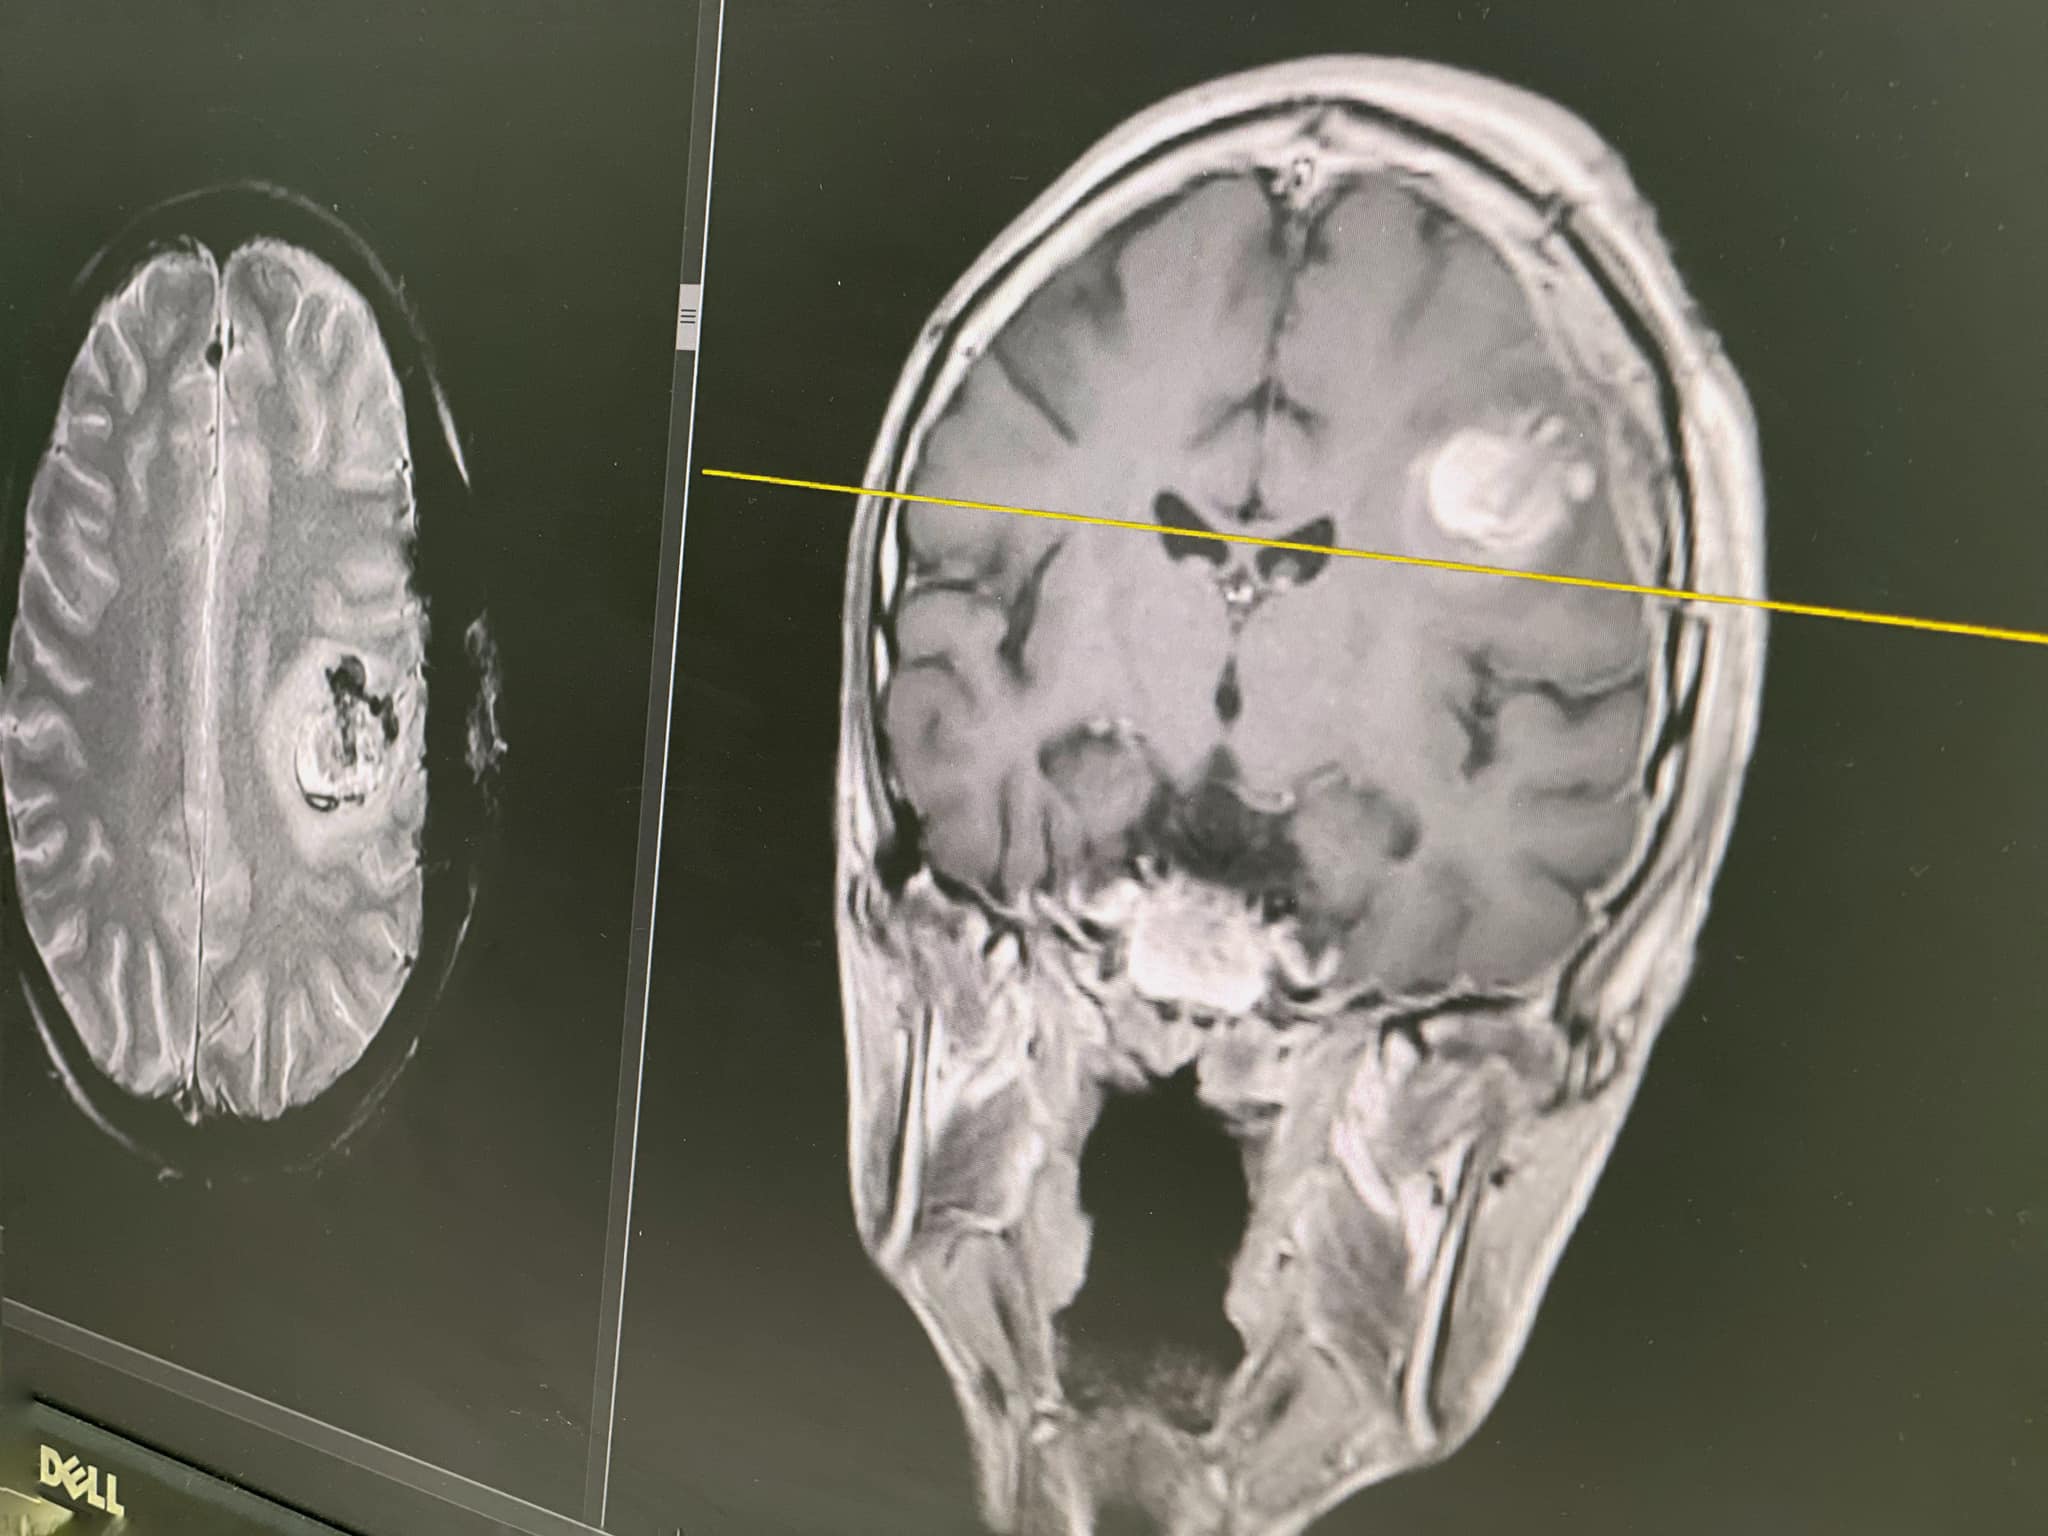

Вперше в Україні дитині зробили операцію на мозку із пробудженням.

Про це повідомили в Першому медичному об’єднанні Львова.

Під час найважливішої частини втручання – видалення пухлини – лікарям вдалося розбудити пацієнта – 15-річного Максима із Тернополя. Сама ж операція відбулася в Лікарні Святого Миколая у Львові.

З роками пухлина виросла і напади посилились. Утворення почало тиснути на ділянки мозку, які відповідають за мову і рухи. Виник високий ризик паралічу правої половини тіла. Мама Максима не могла з цим змиритися і звернулась до львівських лікарів. Ті після ретельного обстеження дійшли висновку, що єдиний шанс для Максима - це операція на мозку з пробудженням

А розбудити Максима потрібно було для того, аби контролювати його мову та рухи і не пошкодити ділянки мозку, що за них відповідають. Операція тривала сім годин. Після неї Максим заговорив ще краще, ніж до втручання. Результати МРТ теж обнадійливі: лікарям вдалося повністю видалити пухлину. А гістологічне дослідження показало, що утворення було доброякісним.